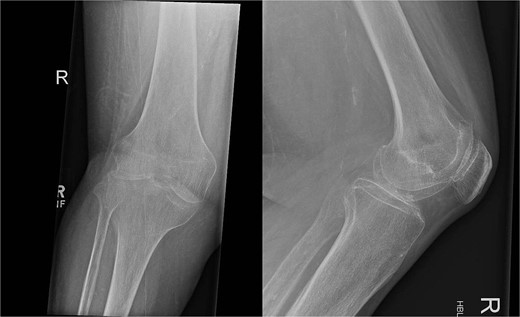

In July 2023, a 75-year-old female patient underwent elective right total knee replacement with patellar resurfacing for osteoarthritis (Fig. 1). Prior to this procedure she was able to mobilize using a walker. Her comorbidities included hypertension, type 2 diabetes mellitus, diverticulosis, Parkinson’s disease, and a body mass index of 33.2. Surgery was uneventful so she was discharged home and requested to continue with rehabilitation (Fig. 2). Two weeks postoperatively she noticed redness and warmth surrounding the knee joint and a further 2 weeks later she felt a “pop” whilst walking. She then presented with a painful, swollen right knee on which she was unable to weight bear. X-rays identified a closed right patellar sleeve fracture. It was assumed that the pain and inflammation was due to the fracture and not due to infection and the decision was taken to treat the fracture non-operatively. The knee was splinted, and she was allowed to touch weight bear with a frame.